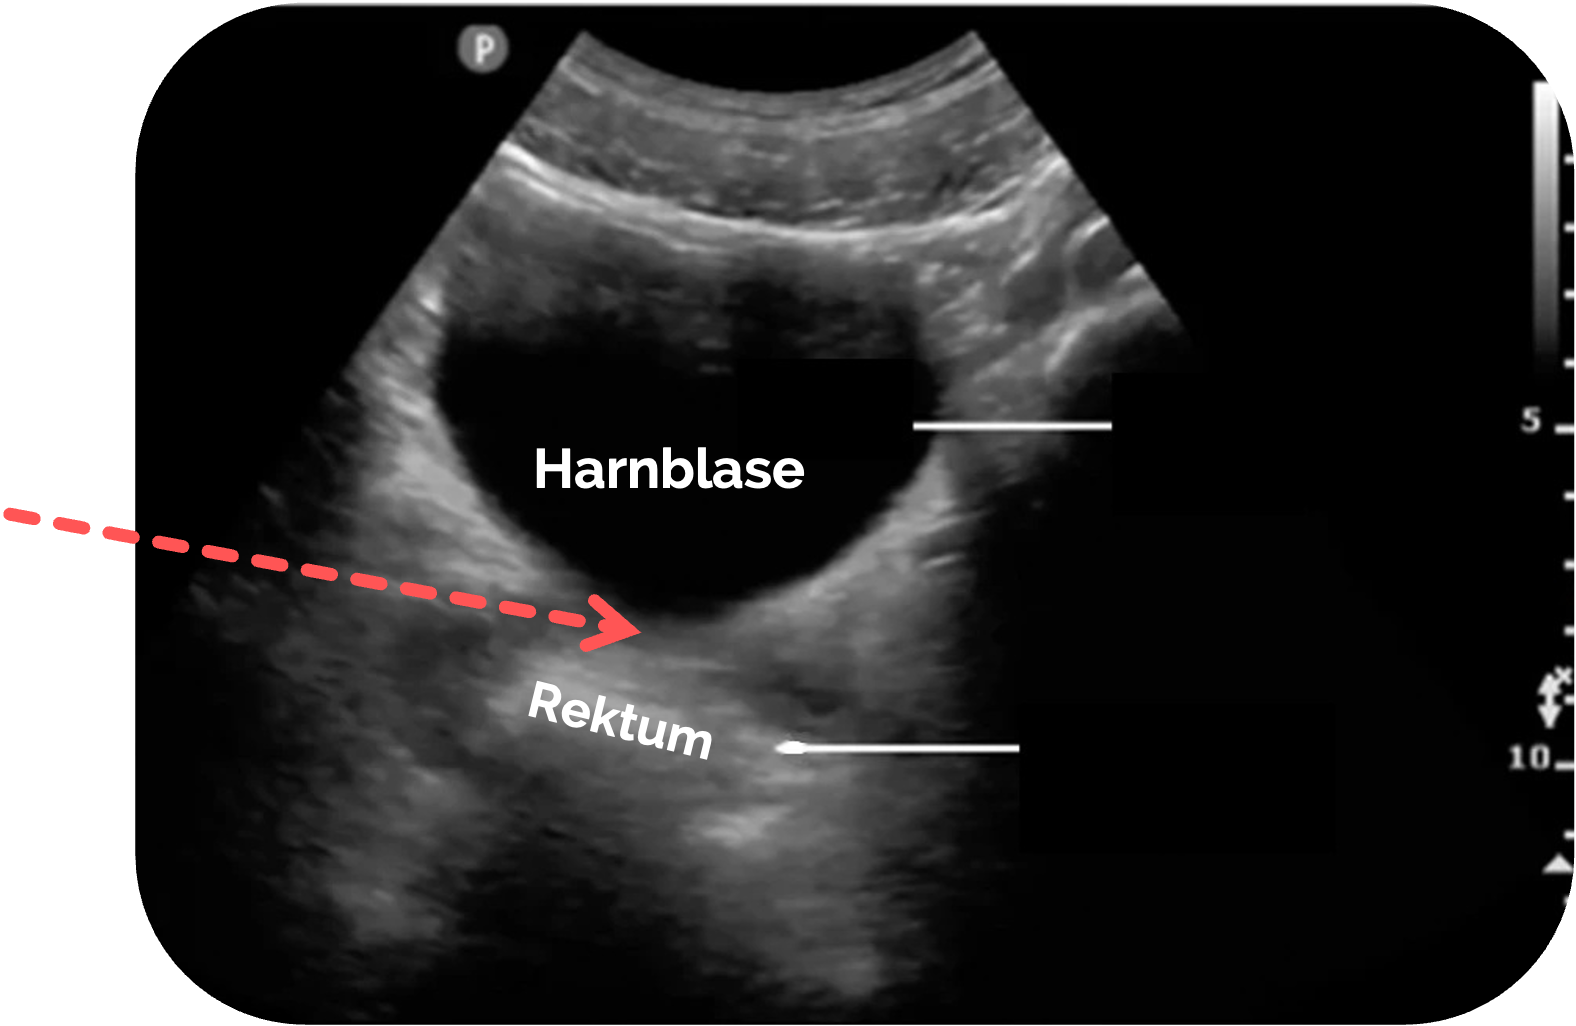

Orientierung beim Mann:

- Harnblase ebenfalls als Fenster

- Rektovesikaler Raum direkt dorsal der Blase

(siehe roter Pfeil) - Rektum

AchtungWird die Sonde zu weit nach kaudal gekippt, können die Samenbläschen mit freier Flüssigkeit verwechselt werden! (siehe folgende Abschnitte)

Figure 2 aus Fasseaux, A., Pès, P., Steenebruggen, F. et al. Are seminal vesicles a potential pitfall during pelvic exploration using point-of-care ultrasound (POCUS)?. Ultrasound J 13, 14 (2021). https://doi.org/10.1186/s13089-021-00209-7. Es wurden der rote Pfeil und die Beschriftungen hinzugefügt.

Figure 2 aus Fasseaux, A., Pès, P., Steenebruggen, F. et al. Are seminal vesicles a potential pitfall during pelvic exploration using point-of-care ultrasound (POCUS)?. Ultrasound J 13, 14 (2021). https://doi.org/10.1186/s13089-021-00209-7. Die Bilder wurden zugeschnitten. Es wurden teilweise die Markierungen und Beschriftungen ergänzt.

a: Blase

Die Samenbläschen stellen sich in der Regel als symmetrische, scharf begrenzte ovale Strukturen dar. Die Lage direkt oberhalb der Prostata ist ein wichtiges Unterscheidungskriterium gegenüber freier Flüssigkeit, die hier in der Regel nicht vorkommt.

Zur besseren Unterscheidung ist die longitudinale Achse sehr hilfreich. Insbesondere, wenn eine unzureichende Blasenfüllung vorliegt, kann man in dieser Schnittebene Harnblase und Rektum